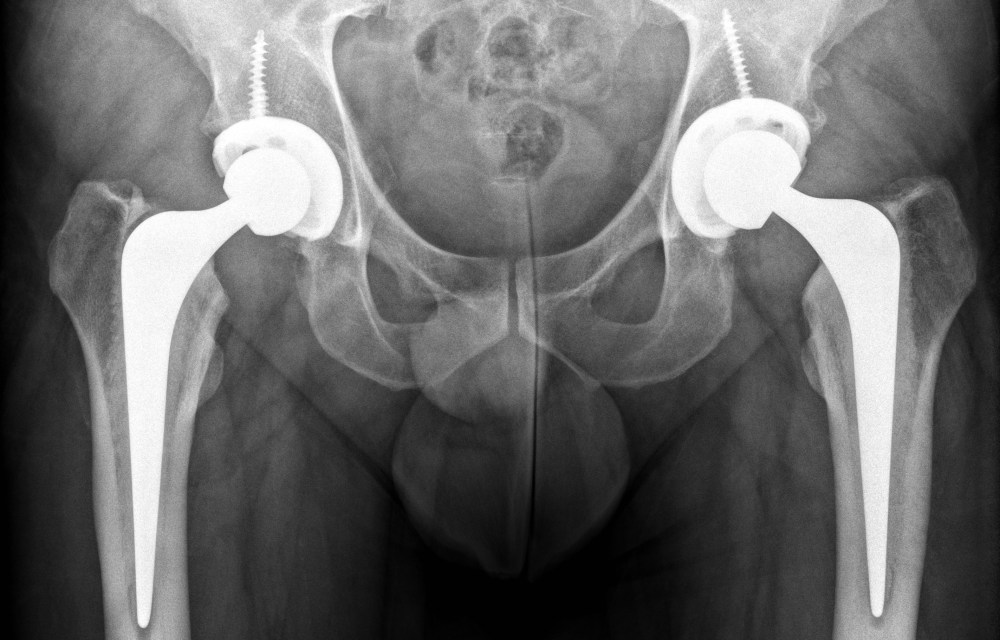

I just decided to share the mechanics that are now happily living inside me. I recently went for my final post-op visit to see my surgeon. They were very pleased with my progress and that the condition of both ‘appliances‘ is almost pristine. So here they are.

So the outcome of the post-op visit was I was signed-off and now hope to have 15-20 years of good use out of these lovely titanium hips.